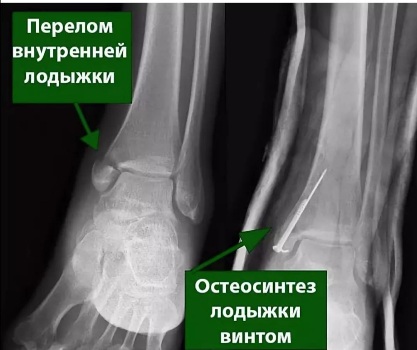

ОСТЕОСИНТЕЗ - это хирургический метод лечения переломов костей, при котором костные отломки фиксируются друг с другом при помощи специальных металлических конструкций (спицы, винты, штифты, гвозди).

Травматологи-ортопеды клиники №1 ВиТерра Беляево работают с металлоконструкциями (винты\спицы).